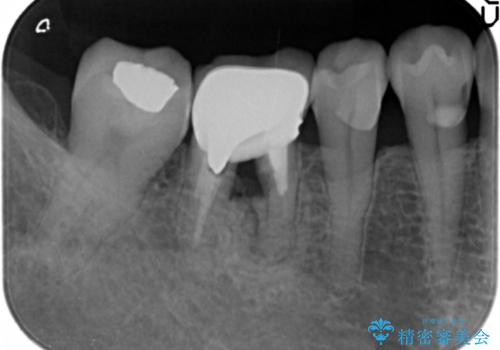

薄い歯質の歯牙に過大な負荷がかかり亀裂を生じ大臼歯分岐部に大きな骨吸収を認め、抜歯を余儀なくされる状態です。

抜歯を行ったのち前後の歯に軽度の動揺があるため、インプラントではなくブリッジによる補綴処置を行い機能回復を行いますが、近心傾斜した第2大臼歯をマイクロインプラントを用いた小矯正を行うことで歯軸方向を改善し、神経を温存した状態でブリッジ製作できるよう前処置を行います。